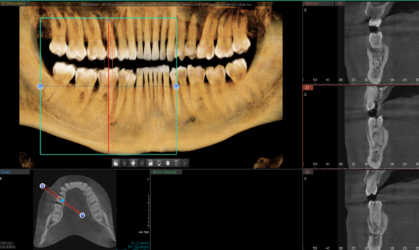

Hi! I have a case I wanted some feedback on. Pt is interested in replacing 24 and 25 with implants. I have attached the cbct below and was wondering what you guys think as far as tx planning. I wanted to place 1 implant with a cantilever for 24 and 25. How would you plan the case given the thin bone? Alveoplasty? GBR? Thank you